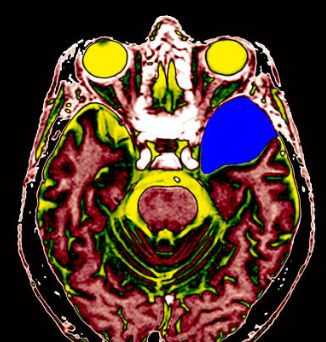

МРТ головного мозга. Т2-взвешенная аксиальная томограмма. Арахноидальная киста. Цветовая обработка изображения.

МРТ головного мозга. Арахноидальная киста полюса левой височной доли. Цветовая обработка.

Кисты головного мозга - это аномалии его развития. При МРТ в СПб мы видим задачу в дифференциальной диагностике с кистозными формами опухолей. При МРТ головного мозга некоторые виды кист, особенно дермоидные, сами напоминают опухоль.